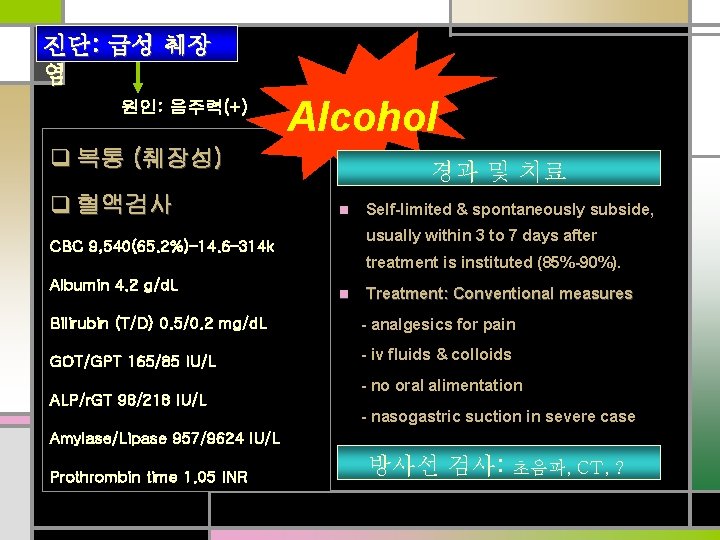

진단: 급성 췌장 염 원인: 음주력(+) Alcohol q 복통 (췌장성) q 혈액검사 경과 및 치료 n usually within 3 to 7 days after CBC 9, 540(65. 2%)– 14. 6– 314 k Albumin 4. 2 g/d. L Self-limited & spontaneously subside, treatment is instituted (85%-90%). n Treatment: Conventional measures Bilirubin (T/D) 0. 5/0. 2 mg/d. L - analgesics for pain GOT/GPT 165/85 IU/L - iv fluids & colloids ALP/r. GT 98/218 IU/L - no oral alimentation - nasogastric suction in severe case Amylase/Lipase 957/9624 IU/L Prothrombin time 1. 05 INR 방사선 검사: 초음파, CT, ?